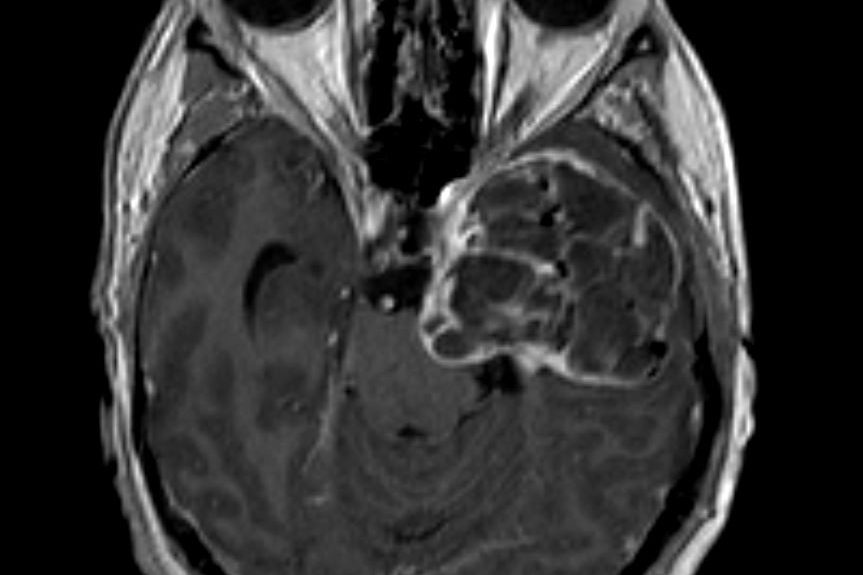

Ασθενής άνδρας, 45 ετών με αιμωδίες του δεξιού ημιπροσώπου, ιλίγγους και κεφαλαλγία. Η μαγνητική τομογραφία εγκεφάλου ανέδειξε εκτεταμένη χωροκατακτητική εξεργασία…